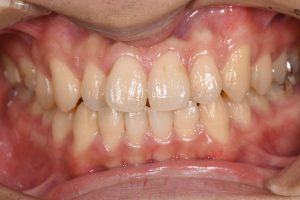

銀歯を全てセラミックにした症例

治療後

この患者様の場合

1回目にカウンセリング

2回目に型取り

3回目にセラミックのセット

の合計3回で治療終了となりました。